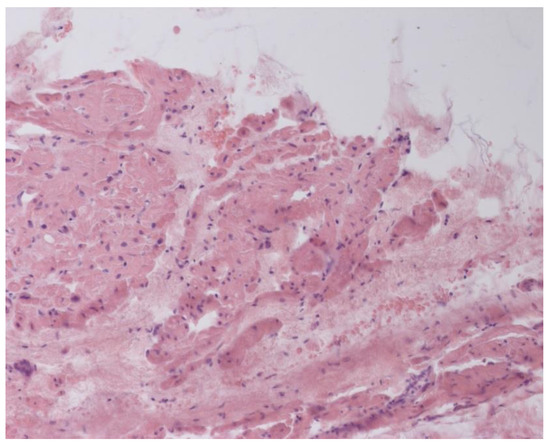

Inflammatory changes in the myocardium were detected in 32 patients (47.8%), including nine patients (28.1%) with lymphocytic infiltration of less than 14 lymphocytes per mm2 (Figure 4 and Figure 5). The data obtained with EMB from RV and IAS were comparable. Inflammatory changes in RV correspond to a similar finding in IAS, while fibrotic changes in RV correspond to the same evidence in IAS. According to the results of immunohistochemical analysis, the virus expression was detected in one of these patients (3.1%). A combination of human herpes simplex virus type 2 and Epstein-Barr was found. No virus expression was detected in the remaining patients.

Figure 5. Endomyocardial infiltration of IAS with lymphocytes, ×200. Hematoxylin-Eosin Staining.